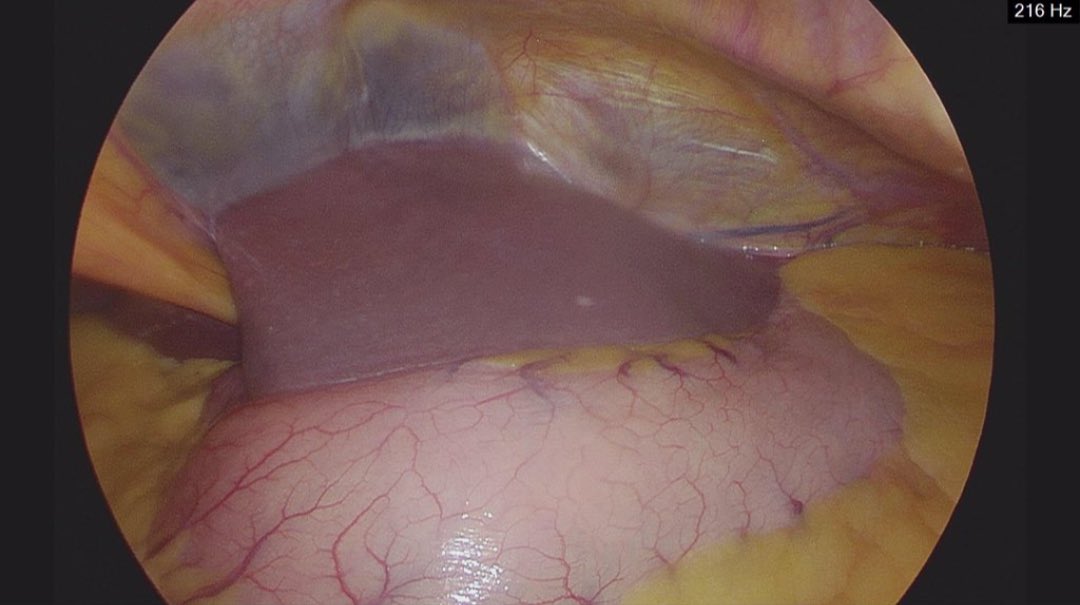

Sustained CO2 excludes oesophageal intubation but does not confirm CORRECT placement of the ETT in the trachea. https://t.co/N8Rjl1542e Thank you @NicholasChrimes & @AndyHiggsGAA for your insights on this case report https://t.co/xRHNphe3bc

#Anaesthesia #anesthesia #airway